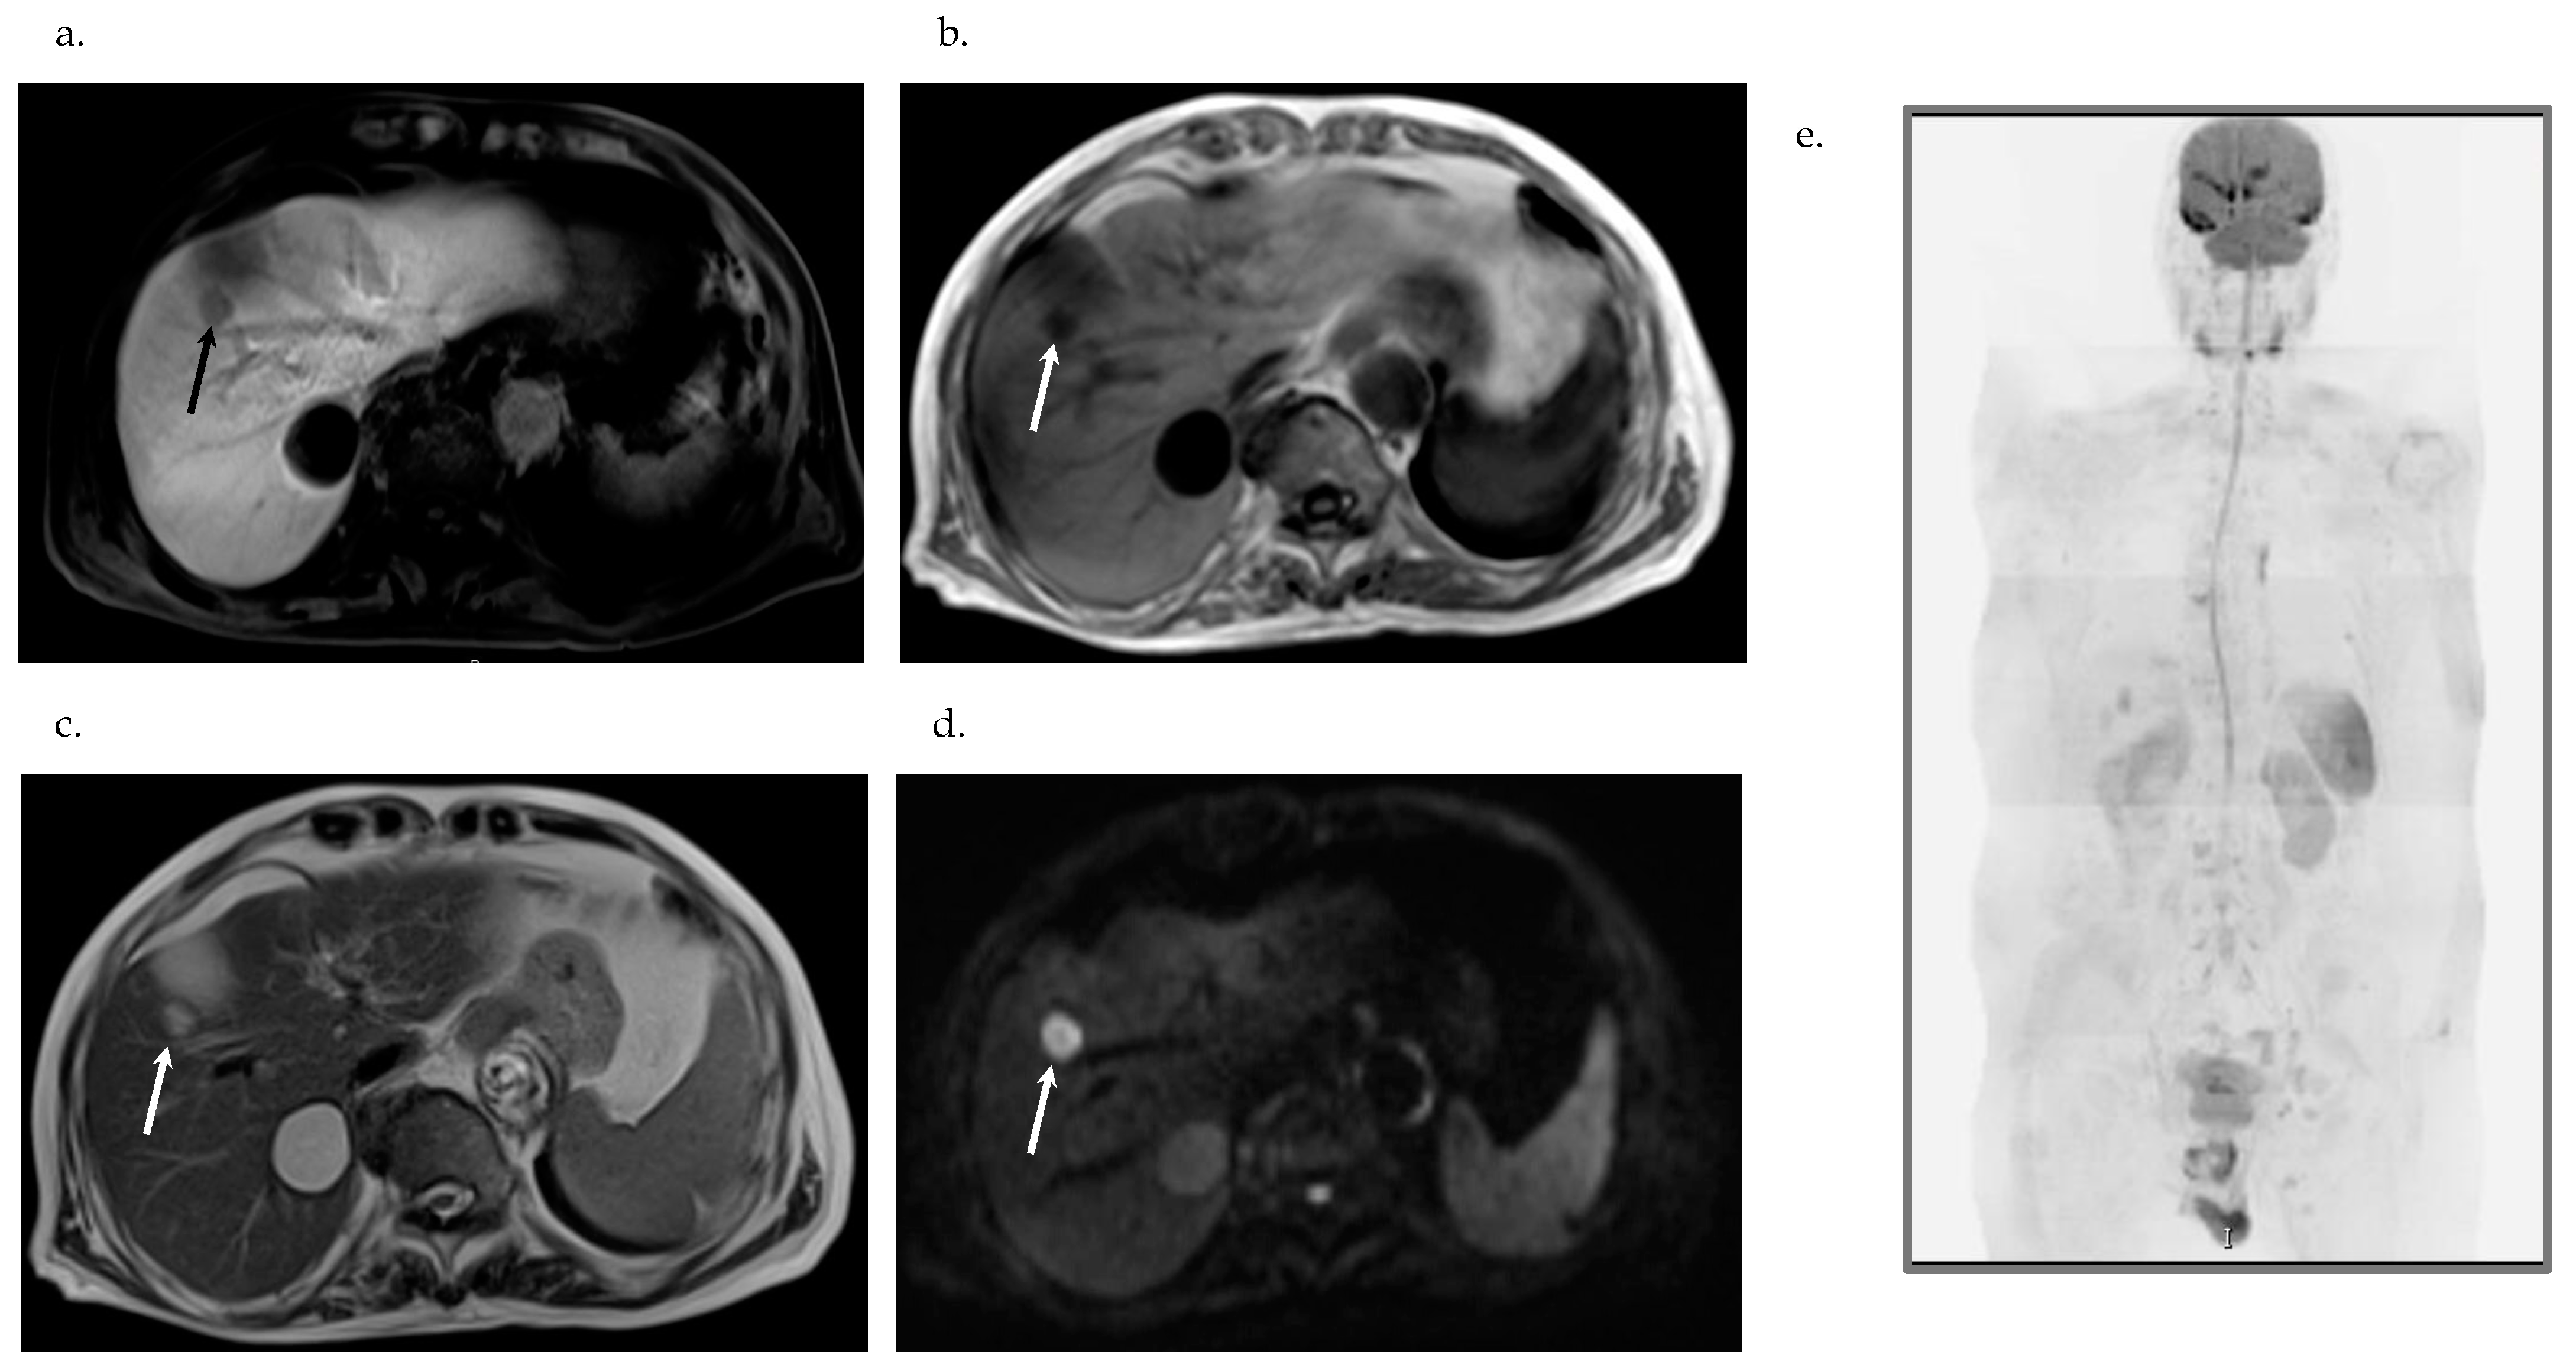

2.6. Imaging Examinations

- Based on pathological findings, the liver tumor was diagnosed as poorly differentiated SCC. Clinically, no primary focus suggesting a metastatic liver tumor in other organs was in evidence; based on GIF, CF, CT and DWIBS, the tumor was finally diagnosed as primary SCC of the liver. Also clinically, the nodule in S6 was a primary SCC lesion and multiple nodules located in S5 and S8 were interpreted as the result of intrahepatic spread from one of the primary SCCs of the liver.

7.3. Imaging